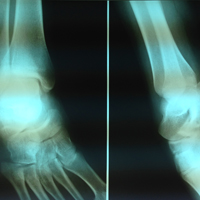

Μετεγχειρητική